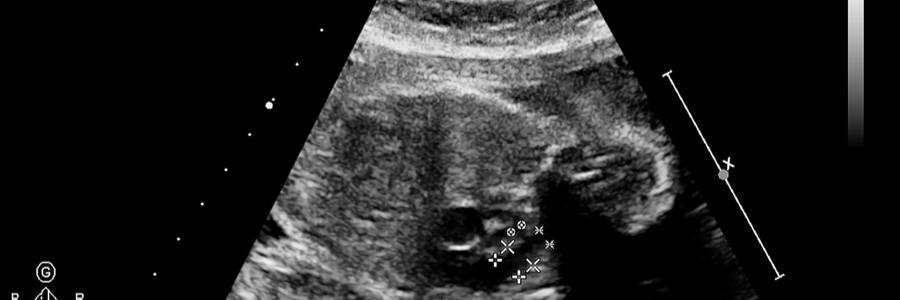

드라마, 영화에서 보면 임산부가 태아가 딸꾹질 한다고 하며 행복해하는데, 이 느낌을 처음 느끼는 임산부라면 신기하고 사랑스럽기도 하지만 한편으로는 태아가 딸꾹질을 멈추지 않을 경우 걱정을 하기도 합니다. 태아가 딸꾹질을 왜 하는지 알아보겠습니다.

태아의 딸꾹질은 횡경막이 발달하면서 하게 되는데 숨을 쉴 때 횡경막이 움직이는 것과 같이 태아가 건강하게 잘 자라고 있다는 신호입니다.

태아는 엄마의 양수 안에 있기 떄문에 숨을 쉴 수 없습니다. 하지만 양수를 삼켰다가 뱉는 것을 반복하는데요. 이때 딸꾹질을 느끼게 됩니다.

많은 임산부들은 정기 검진을 가게 되는데 검진 시 꼭 의사에게 이것저것 물어보며 궁금증을 해소하고 걱정된다면 초음파를 실행하는 것도 좋습니다.